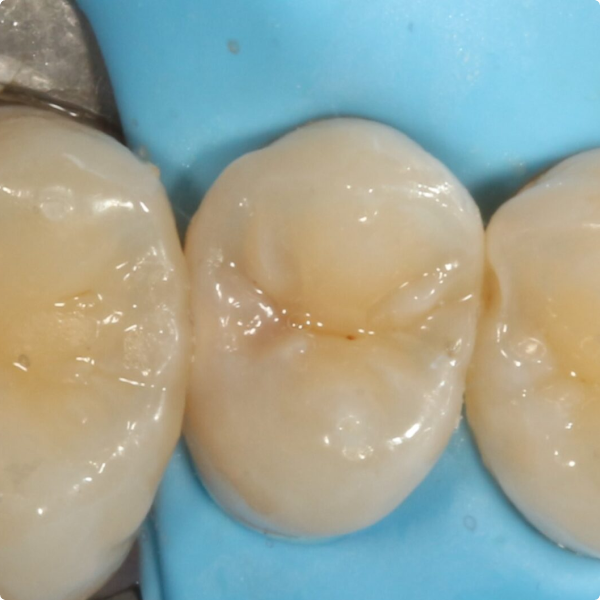

The restoration was straightforward and efficient, taking less time than a traditional amalgam or multi-stage composite workflow. By using Stela, Dr Shankla reduced instrument use and the number of procedural steps making the treatment more cost- and time-effective. After placement, she allowed a few minutes for self-curing, then completed final trimming and polishing all without the need of a curing light.

The patient reported no postoperative sensitivity, and no complications emerged. Because the patient is considered higher risk for future dental issues, Dr Shankla scheduled a follow-up X-ray in one year to assess the restoration’s durability.